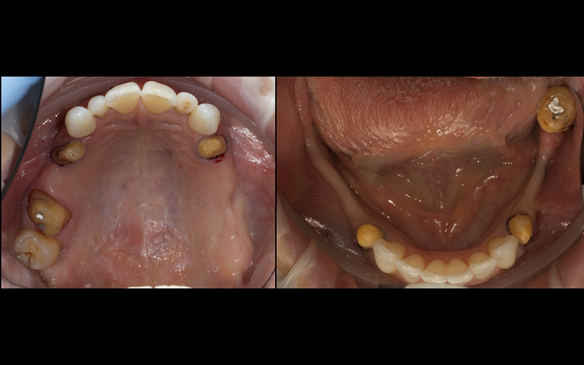

This newsletter describes in step by step detail Angela's transition through immediate partial dentures to crown supported definitive metal based dentures.

- Generalised Periodontitis; Stage 4, Grade C, Currently Unstable. Risk Factors: Type 1 diabetes. 16, 17 - hopeless prognosis. 14, 24, 26, 27, 34, 37, 44 - guarded prognosis

- Poor marginal fit and poor appearance of crowns and bridgework

The clinical situation and treatment process is shown in detail below with photographs. I (Finlay Sutton) provided the clinical work and Rowan Garstang provided the technical work.